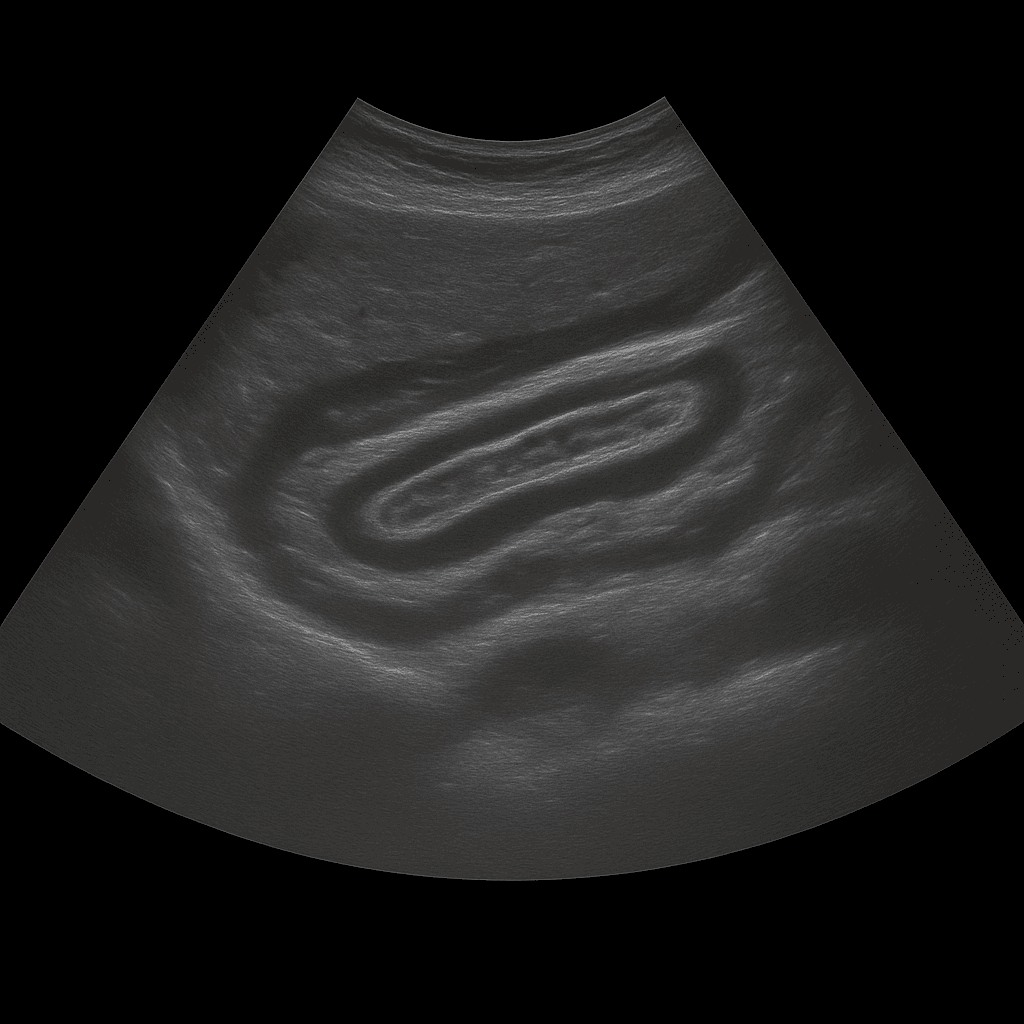

An abdominal ultrasound is used to examine the internal organs of the abdomen such as the liver, gallbladder, bile ducts, pancreas, spleen, kidneys and bladder. The examination is performed by a specialist in radiology and provides detailed images in real time. Abdominal ultrasound is used to investigate pain, swelling, changed blood tests or suspected disease in the abdominal organs.

The examination is performed while you lie on your back. A gel is applied to the skin and the doctor moves the ultrasound probe over the abdominal area to assess the internal organs. The examination takes about 20–30 minutes and is completely painless. For the best image quality, you should fast for 4–6 hours beforehand, as air and food in the intestine can affect the image result. If necessary, the bladder is also examined when full to assess the outflow of the kidneys.